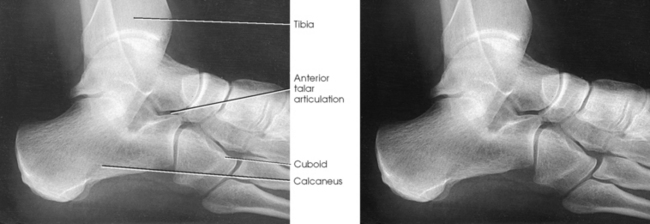

Isherwood1 devised a method for each of the three separate articulations of the subtalar joint: (1) a medial rotation foot position to show the anterior talar articulation, (2) a medial rotation ankle position to show the middle talar articulation, and (3) a lateral rotation ankle position to show the posterior talar articulation. Feist and Mankin2 later described a similar position.

Structures shown: The resulting image shows the anterior subtalar articulation and an oblique projection of the tarsals (Fig. 6-86). The Feist-Mankin method produces a similar image representation.

Structures shown: The resulting image shows the middle articulation of the subtalar joint and an “end-on” projection of the sinus tarsi (Fig. 6-88).

Structures shown: The resulting image shows the posterior articulation of the subtalar joint in profile (Fig. 6-90).